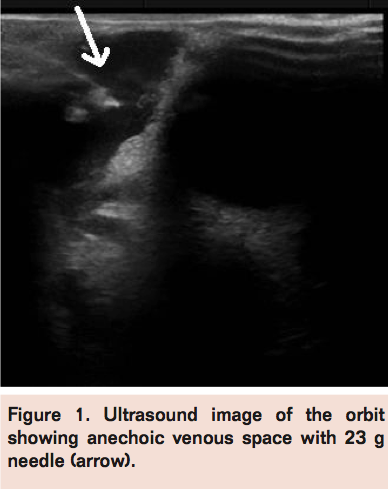

Free reflux of blood was noted. Venography was performed with 50% contrast, which was injected under blank roadmap to assess the volume (Figure 2). The estimated volume was approximately 4 mL. There was no immediate opacification of the veins, suggesting that the venous malformation was a sequestered type. Sclerotherapy was performed using 2 mL of sodium tetradecyl sulfate (Setrol 3% W/V) and 2 mL of contrast. There was no extravasation noted during the procedure. At the end of sclerotherapy, there was increase in the orbital swelling.